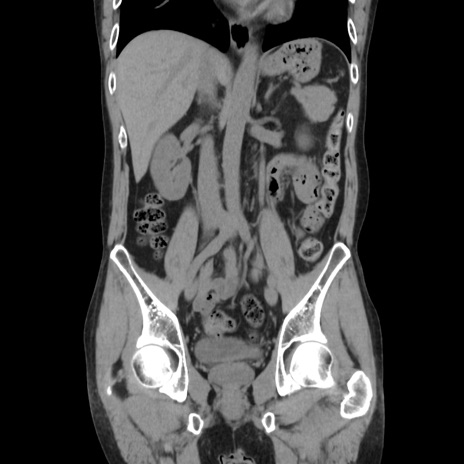

症例37(冠状断像)

【症例】40歳代 男性

【主訴】腹痛

【現病歴】4時間ほど前に電車に乗車中に臍部上より腹痛出現。徐々に増悪し起立困難となり、救急外来受診。生ものは数日食べていない。今朝お雑煮を食べた。

【身体所見】BT 36.8℃、BP 117/84mmHg、HR 91/min、SpO2 97%、苦悶様、腹部:臍上部広範囲圧痛あり、反跳痛±

【データ】WBC 8100、CRP 0.03